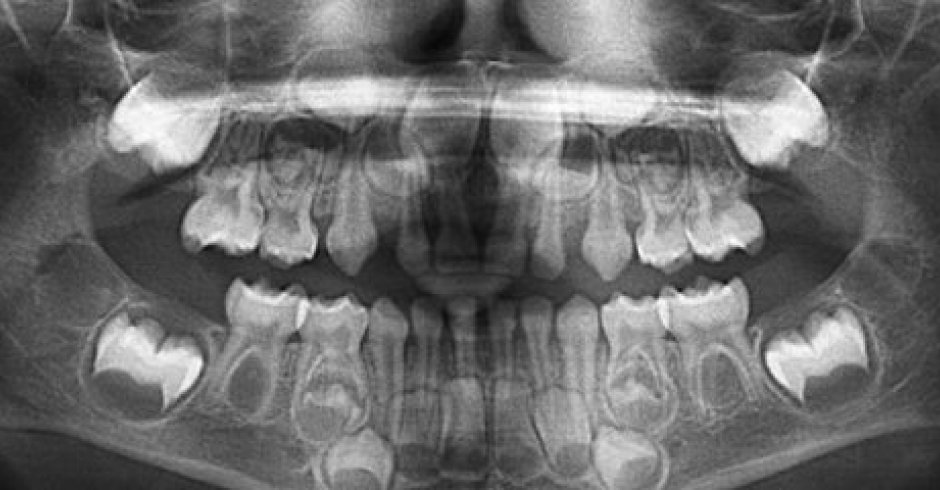

Panorámica